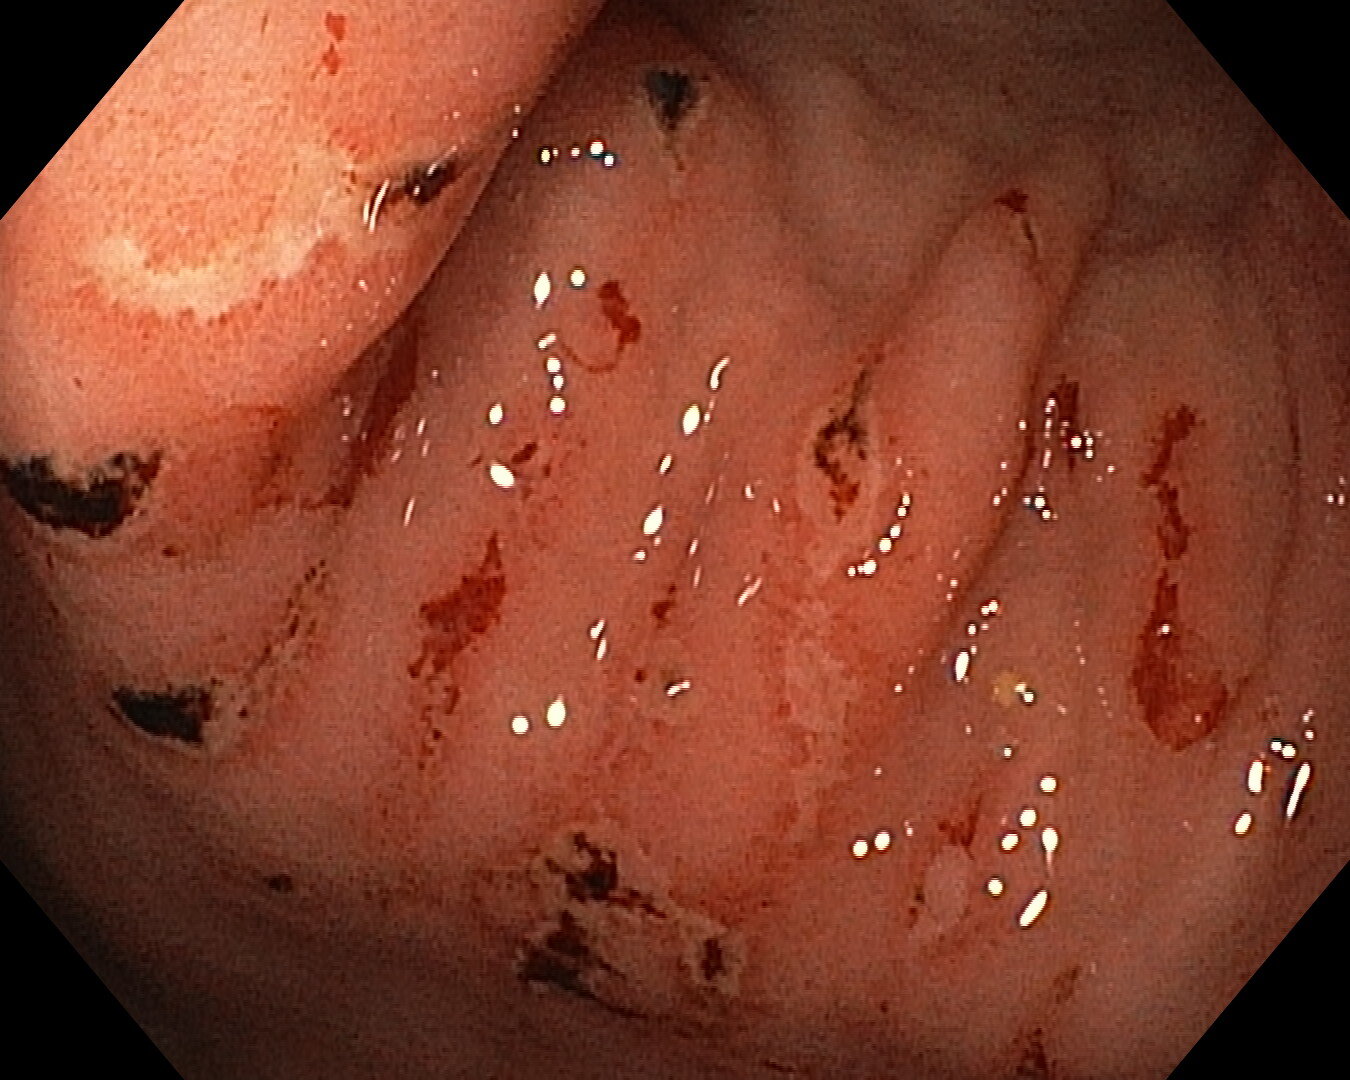

В качестве примера: на фото эндоскопическая картина химического ожога слизистой желудка, осложнившегося кровотечением. Пациентка была доставлена ко мне на гастроскопию после того, как отобедала с тарелкой, помытой азелитом. Тарелку плохо ополоскали после ПАВа. После недели лечения выписана домой в удовлетворительном состоянии, через месяц всё зажило.